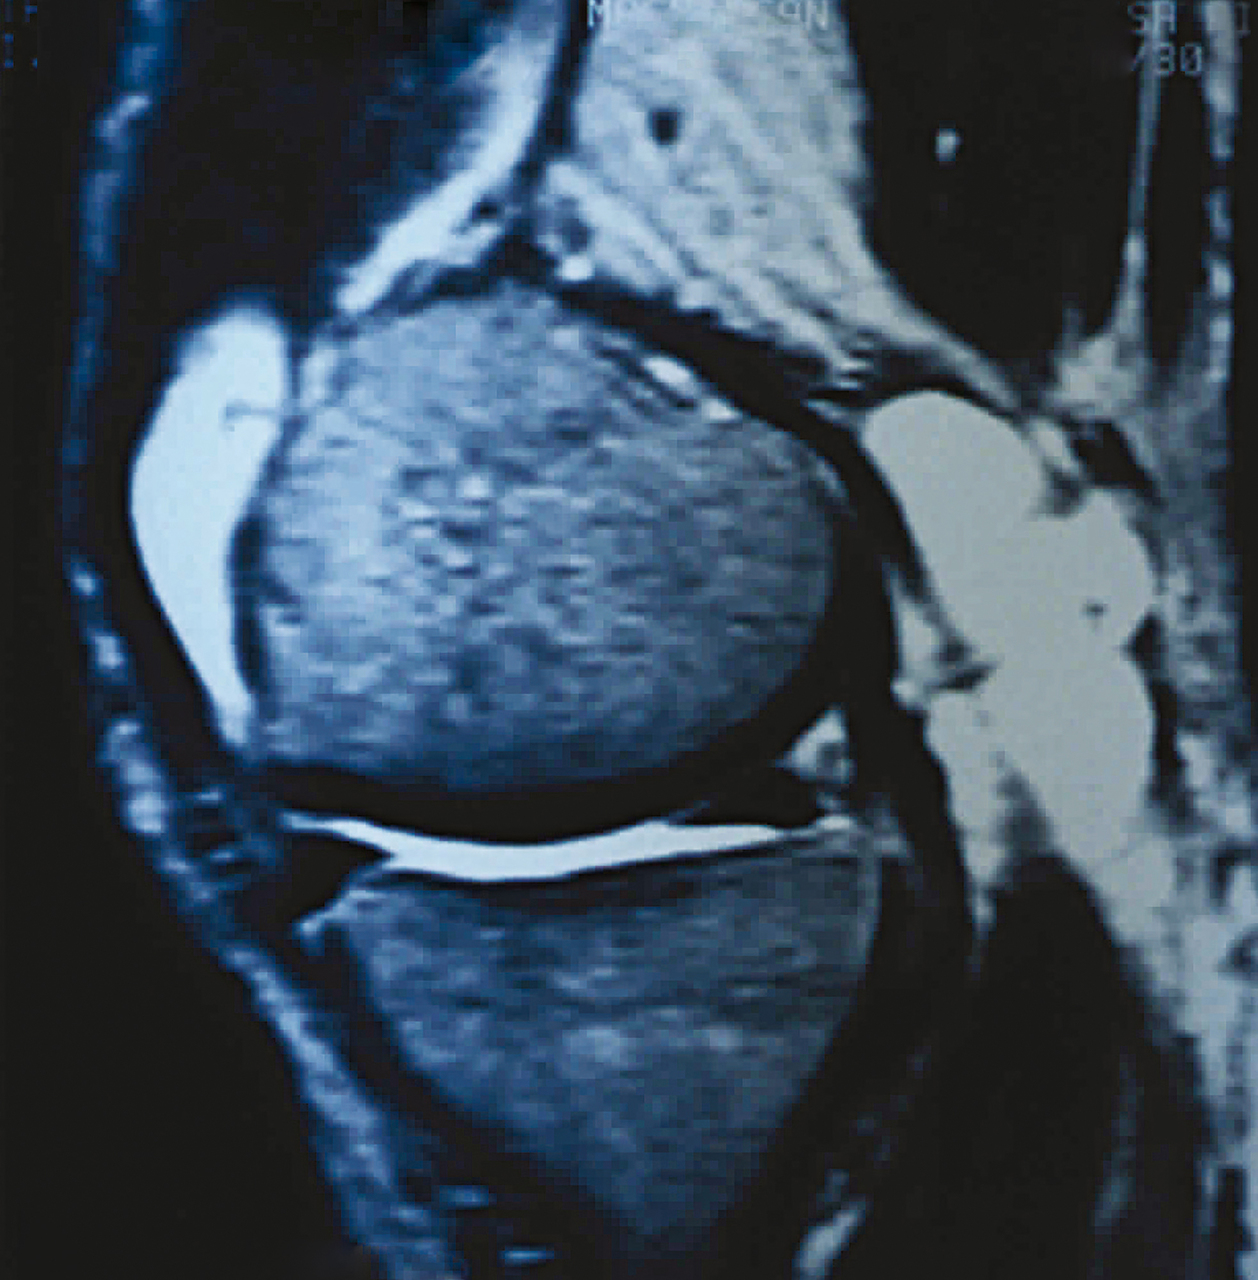

Quel est votre diagnostic ? Arthrite septique Kyste poplité Il s'agit d'un kyste poplité.Pour en savoir plus : Delannoy G, Vallet CE. Kyste poplité. Rev Prat 2017;67(2):166. Dehamchia-Rehailia N, Jelin G, Fardellone P, Goëb V. Arthrose. Rev Prat 2015;65(5):709-18. Arthrite microcristalline Synovialosarcome Anévrisme poplité OK Valider mes réponses